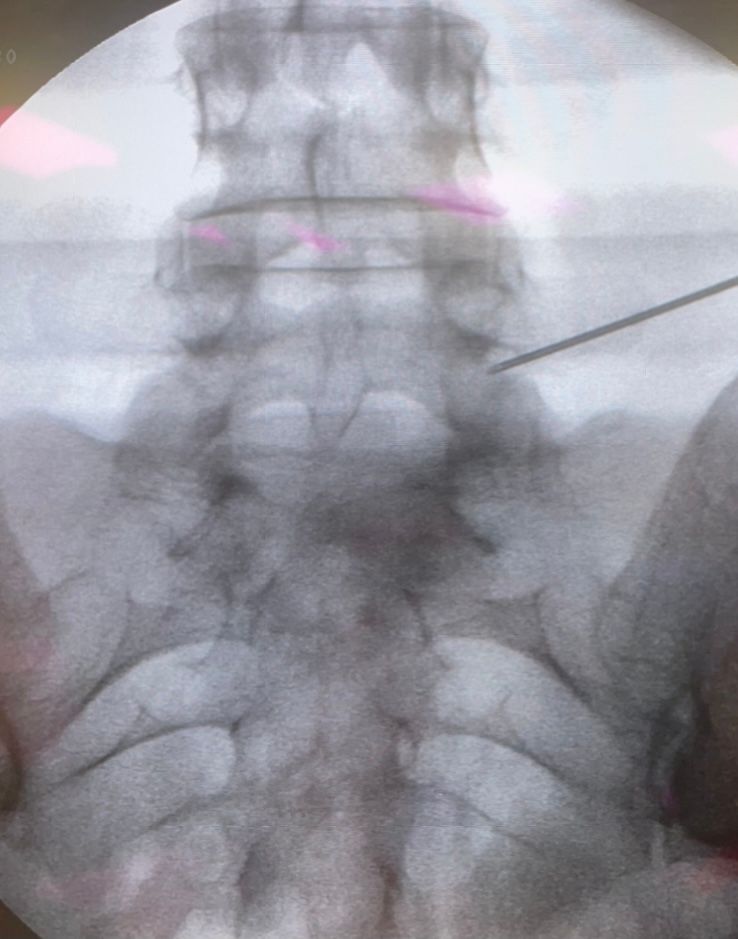

Starszy Asystent w Klinicznym Oddziale Neurochirurgicznym oraz Poradni Neurochirurgii Wojewódzkiego Szpitala Specjalistycznego im. św. Barbary nr 5 w Sosnowcu. Konsultant Kliniki Neurologii Szpitala Klinicznego nr 1 w Zabrzu. Absolwent Wydziału Lekarskiego Śląskiego Uniwersytetu Medycznego w Zabrzu. Staż podyplomowy odbył w latach 2010-2011 w Oddziale Neurochirurgii WSS nr 4 w Bytomiu. W 2018r. złożył egzamin specjalizacyjny po zakończeniu szkolenia w ramach rezydentury w WCM Opole. W 2019 roku uzyskał stopień doktora nauk medycznych. Specjalizuje się w kompleksowym leczeniu schorzeń kręgosłupa (dyskopatia, stenoza kanału kręgowego, kręgozmyk) oraz neuroonkologii. Szczególny zakres działań medycznych to nowoczesne, małoinwazyjne operacje kręgosłupa z wykorzystaniem technik endoskopowych (mikrodiscektomia - implanty rozprężalne), przezskórnych stabilizacji oraz mikrochirurgicznych dekompresji. Wykonuje procedury iniekcyjne; discoGEL, GelSTIX, kriolezje oraz blokady przeciwbólowe kręgosłupa odcinka szyjnego, lędźwiowo-krzyżowego a także stawów krzyżowo-biodrowych, które odgrywają istotną rolę w procesie diagnostyczno-leczniczym wielu zespołów bólowych. Na co dzień przeprowadza operacje w ramach kontraktu z NFZ. Członek Polskiego Towarzystwa Neurochirurgów oraz Polskiego Towarzystwa Chirurgii Kręgosłupa. Uczestnik wielu krajowych i zagranicznych kursów neurochirurgicznych, m.in. w Czechach, Słowacji, Niemczech, Włoszech, Danii, Austrii, Szwajcarii i USA. Autor licznych publikacji naukowych.

Zdjęcia i filmy